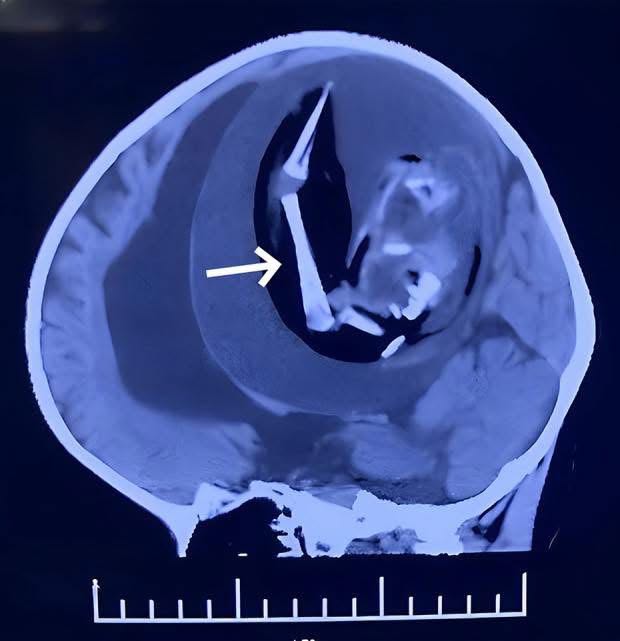

จึงถูกส่งมาตรวจ CT สมอง

พบว่า

ในสมองของเด็ก

มี “ถุงขนาดใหญ่มาก”

ลักษณะคล้ายน้ำคร่ำ

และภายในถุงนั้น

มีโครงสร้างที่เห็นเป็น กระดูกแขนขาชัดเจน

ขนาดก้อนโดยประมาณ

15 × 13 × 12.5 มิลลิเมตร

ฝังตัวอยู่ในสมอง

และเบียดอัดเนื้อสมองรอบข้างอย่างรุนแรง